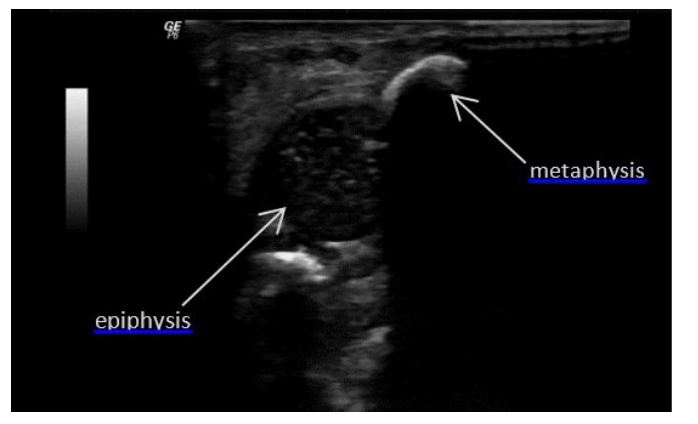

On the second day of life, a shoulder ultrasound was performed to confirm the diagnosis. Instead, it revealed a separation of the proximal humeral epiphysis from the diaphysis, classified as Salter-Harris type I. The proximal end of the humeral shaft was found to be lateral and posterior to the humeral head (Figure 2).

Figure 2 Longitudinal sonography of the right shoulder showing separation of the left humeral epiphysis from the metaphysis.